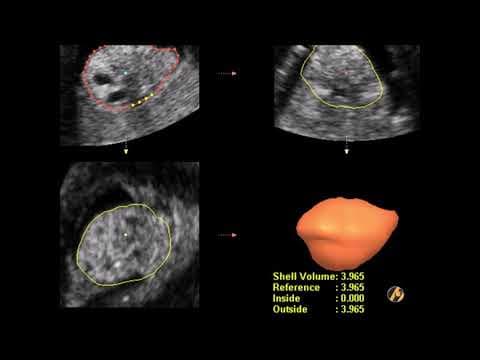

• 2D ultrazvuk = standardna ravna slika (sve poliklinike imaju) • 3D ultrazvuk = trodimenzionalna slika fetusa (detaljnije vide se anomalije) • 4D ultrazvuk = 3D slika u pokretu (vidite fetus kako se mijenja u realnom vremenu) • 5D/HD Live ultrazvuk = najnaprednija tehnologija s detaljima kao fotografija U Poliklinici Harni koristimo 3D, 4D i 5D ultrazvuk, što nam omogućava ranom otkrivanju anomalija i pružanju roditeljima jasne slike bebe prije poroda.